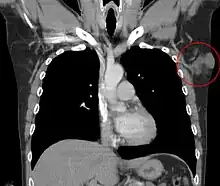

Additional images

Subcutaneous tissue infiltration (i.e. "honeycomb" growth pattern)